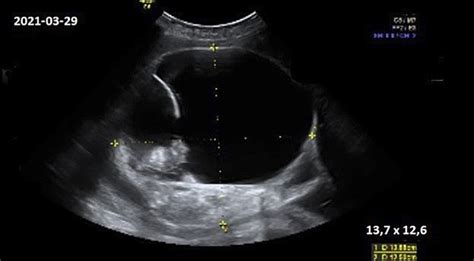

- Policistinės kiaušidės ultragarse: Kiaušidėse nustatomas didelis skaičius mažų folikulų (dažniausiai daugiau nei 20) arba padidėjęs kiaušidės tūris (didesnis nei 10 ml).

Ultragarsinis Tyrimas

Atliekamas transvaginalinis ultragarsas, siekiant įvertinti kiaušidžių dydį ir morfologiją. Policistinė morfologija nustatoma, kai kiaušidėje yra daug mažų folikulų (≥ 20 viename kiaušidės metre) arba kiaušidės tūris viršija 10 ml. Anti-Müllerio hormono (AMH) lygio matavimas kraujyje taip pat gali būti informatyvus.